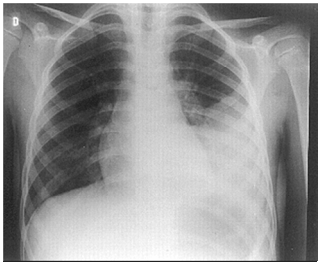

Um homem de 37 anos é internado com febre, calafrios, tosse produtiva e falta de ar de início há 1 dia. Está hemodinamicamente estável, saturando 94% com cateter nasal de oxigênio 2 L/min.

A sua radiografia de tórax mostra:

O tratamento é iniciado com ceftriaxona e claritromicina. Após 24 horas, são identificadas duas hemoculturas positivas para Streptococcus pyogenes. Nesse caso, o tratamento de escolha é